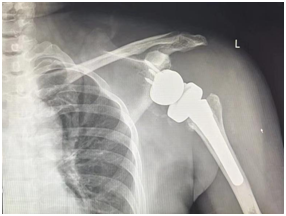

逐波踏浪谋跨越,创新发展万象新。2024年2月23日,我院骨科中心关节与足踝病区团队联合王坤正主委厦门工作室团队,成功完成我院首例“反置式人工全肩关节置换”手术,为一位终末期肩关节疾病患者带来了“新生”。通过精细的手术技巧和专业的术后护理,患者目前恢复良好,逐步恢复日常生活。

患者陈女士长期饱受夏科氏关节病的困扰,左肩关节反复肿胀,肩袖正常组织完全破坏,肩关节结构与功能丧失,严重影响生活质量。患者尝试了多种保守治疗方法后,慕名前来我院骨科中心关节与足踝病区要求手术治疗。考虑到该患者肩关节病理结构的复杂性与手术技术难度,杨佩主任团队邀请王坤正主委厦门工作室王少杰主任团队协助完成手术,骨科中心关节与足踝病区医护团队与麻醉科罗斌医生、手术室李娅主管护师、严鑫隆护士高效配合,成功完成我院首例“反置式人工全肩关节置换”手术。目前,陈女士已经开始了康复训练并逐步恢复日常生活。

我院骨科中心名誉主任、中华医学会骨科学分会候任主任委员王坤正教授介绍,反肩置换手术是一种针对多种复杂终末期肩关节疾病的有效治疗方案。该术式依托新型肩关节人工假体系统可以有效实现肩关节功能的全面恢复。杨佩主任介绍,反肩置换手术的适应症广泛,包括终末期肩袖病变、假体翻修术、肱骨近端复杂骨折及畸形愈合、肩关节骨性关节炎及类风湿关节炎、骨肿瘤等。此次手术的成功不仅为陈女士带来了希望,也为更多肩关节疾病患者提供了新的治疗选择。